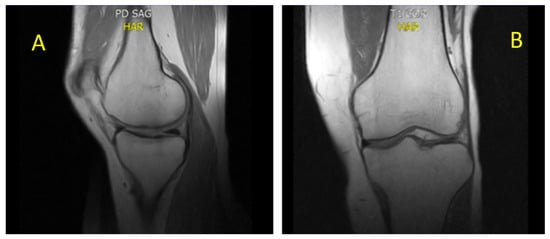

- CASE 1: A CML patient under dasatinib and imatinib treatment

- CASE 2: 60-year-old patient with imatinib therapy

- CASE 3: 66-year-old patient with imatinib therapy